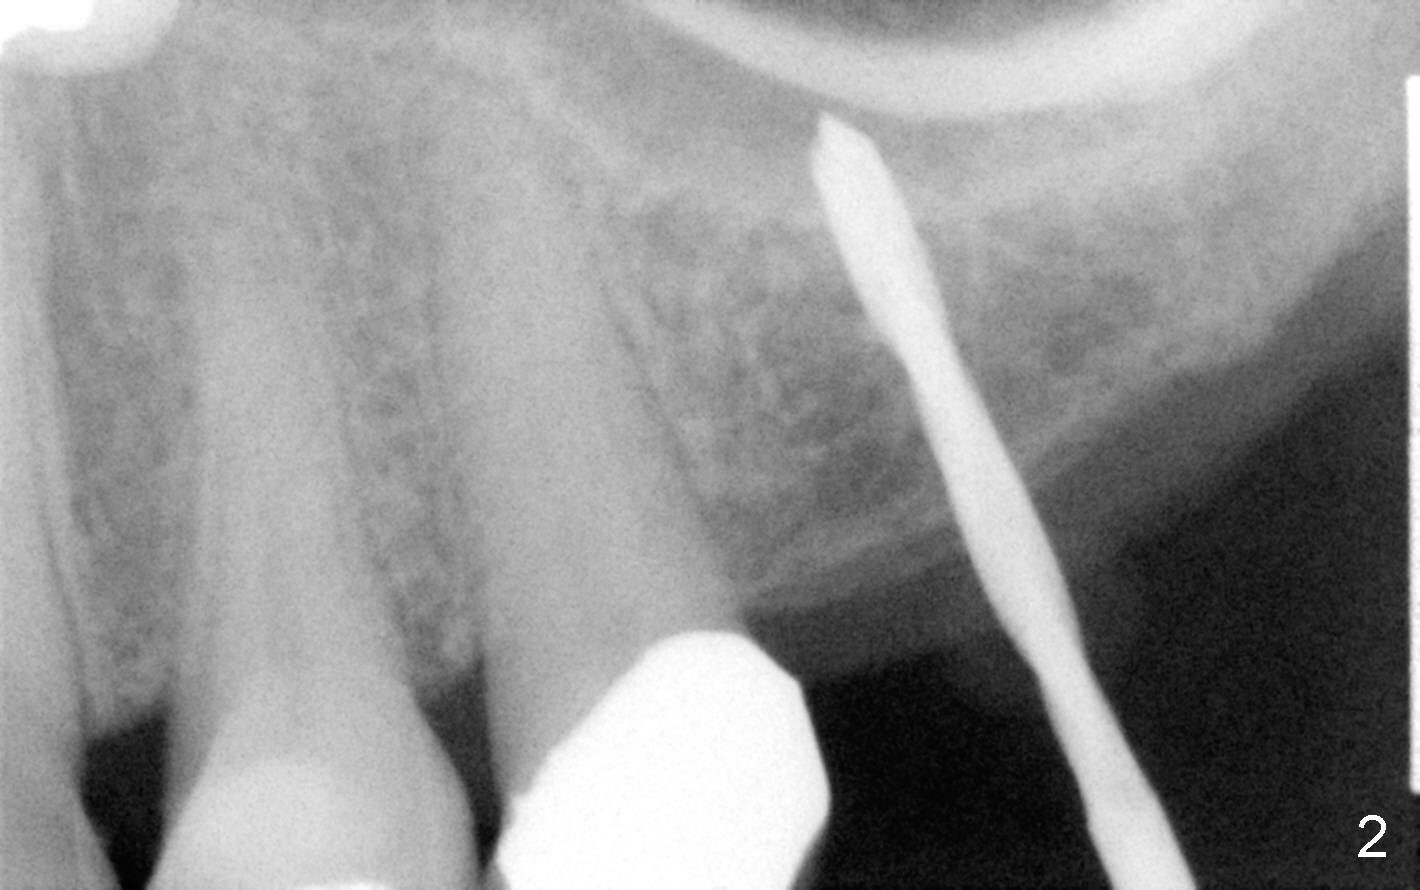

Fig.2 shows a 1.6 mm pilot drill at the depth of 11 mm; the tip of the drill penetrates the sinus floor. Bone expanders (2.6, 3.0, 3.4, 3.8 (Fig.3) and 4.3 mm) are used and alternated with tapered osteotomes (3 and 4 mm). The latter are used to break through the sinus floor. Then 4.5x14 mm and 5x14 mm taps are applied to create threads for implant. The second tap has some binding to the bone. Finally 5x14 mm tapered implant is inserted with more than 60 Ncm torque (Fig.4). Although the apical portion of implant (approximately 3 mm) pokes into the sinus, the patient does not experience nasal hemorrhage intra- or post-op.